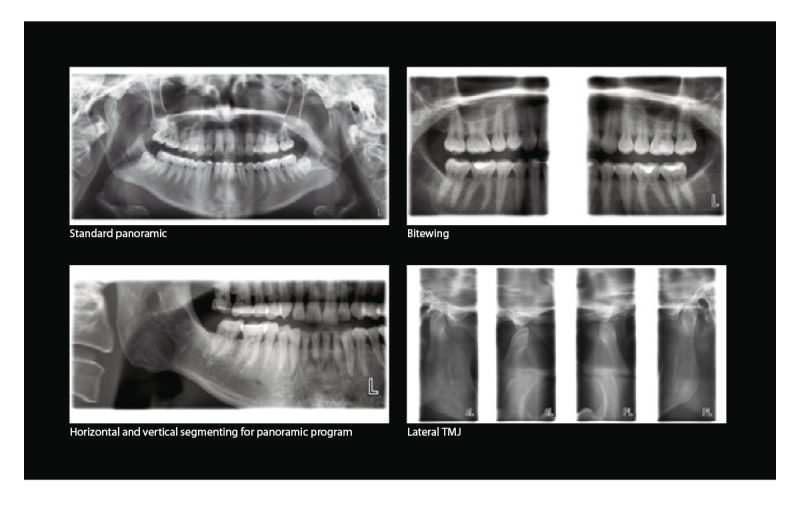

Source: www.meddentonline.pl Planmeca ProOne cena Sklep MEDDENT , • Imaging programs include standard panoramic, sinus imaging, and TMJ. Planmeca ProOne is equipped with a full-colour graphical user interface that helps guide you through procedures with clear texts and symbols

Source: www.burkhartdental.com Planmeca ProOne Digital Panoramic XRay Burkhart Dental Supply , IEC approved (CE marked), UL / CSA approved • located outside the patient area (more than 2m (79 in.) from the X-ray unit) Planmeca ProOne® offers you a wide variety of imaging programs for different radiographic needs